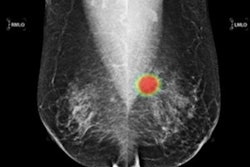

The researchers used version 4.7.2 of the Lunit Insight for Chest Radiography algorithm to analyze 1,135 consecutive patients who had visited the emergency department between January 1 and March 31, 2017, and had received a chest x-ray. The Lunit algorithm analyzes chest x-rays for the presence of pulmonary malignancy, active pulmonary tuberculosis, pneumonia, and pneumothorax, according to the authors.